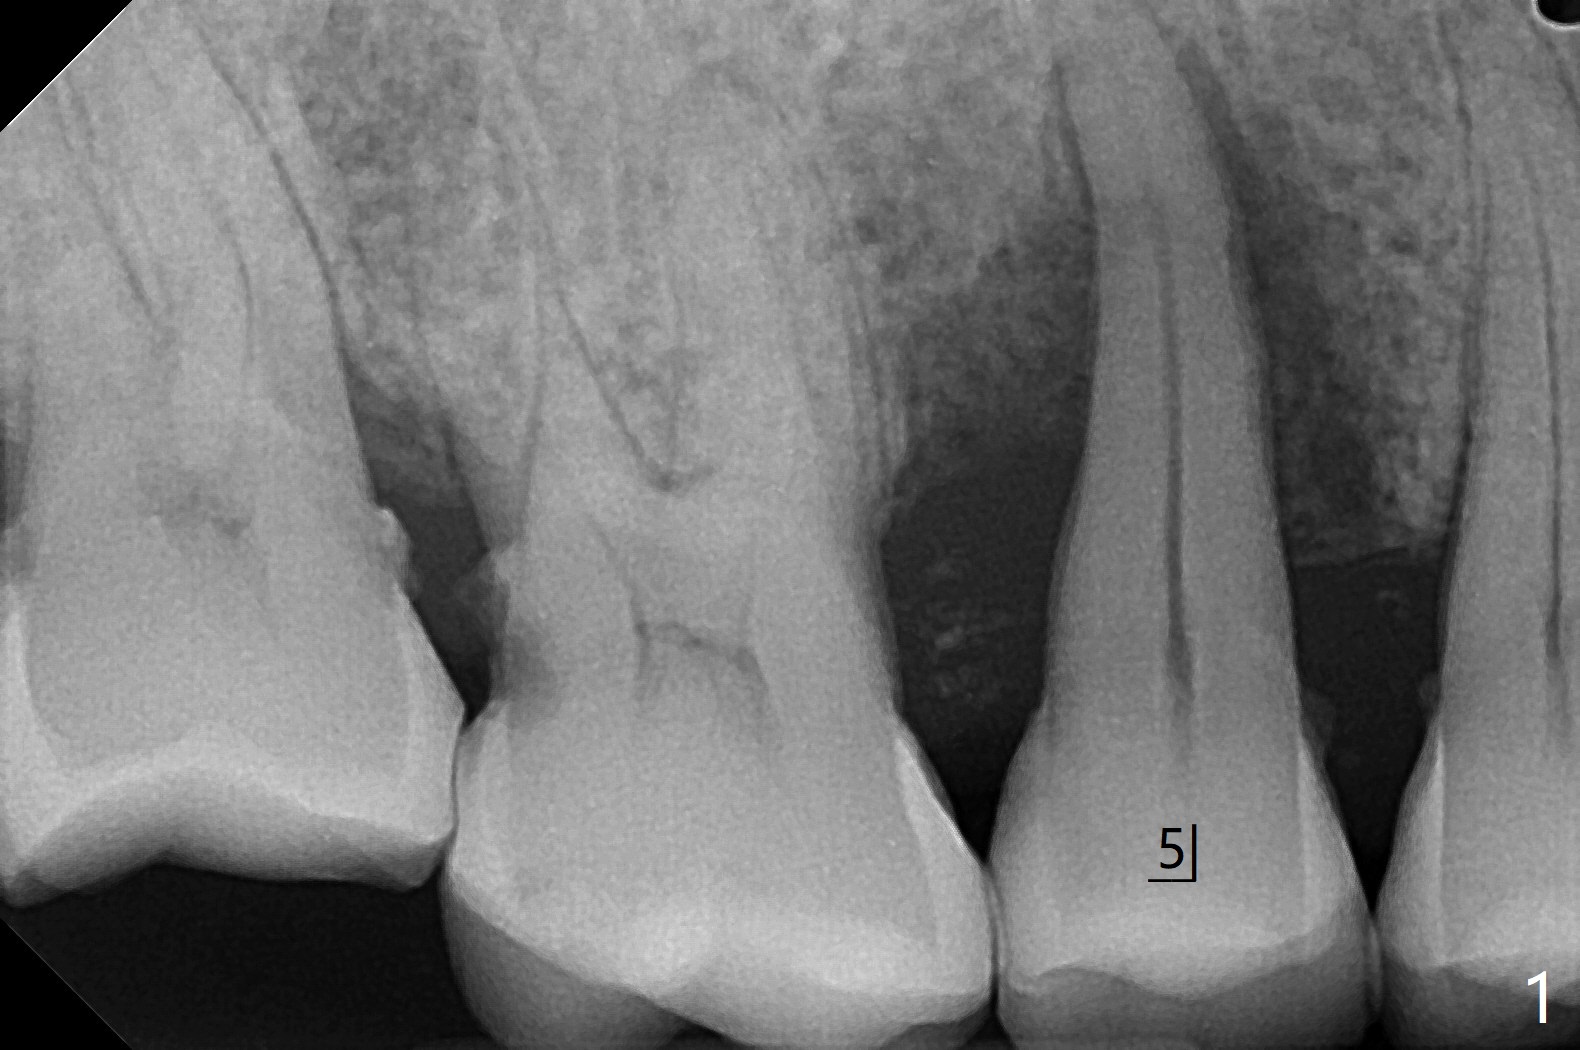

61岁女,右下六缺失,要求拔除纵裂右上五(图一:舌侧部分松动),刮除大量肉芽组织后,植入皮质骨骨粉(图二,三),覆盖6个月吸收膜,4-0 PGA 缝线,牙周敷料。